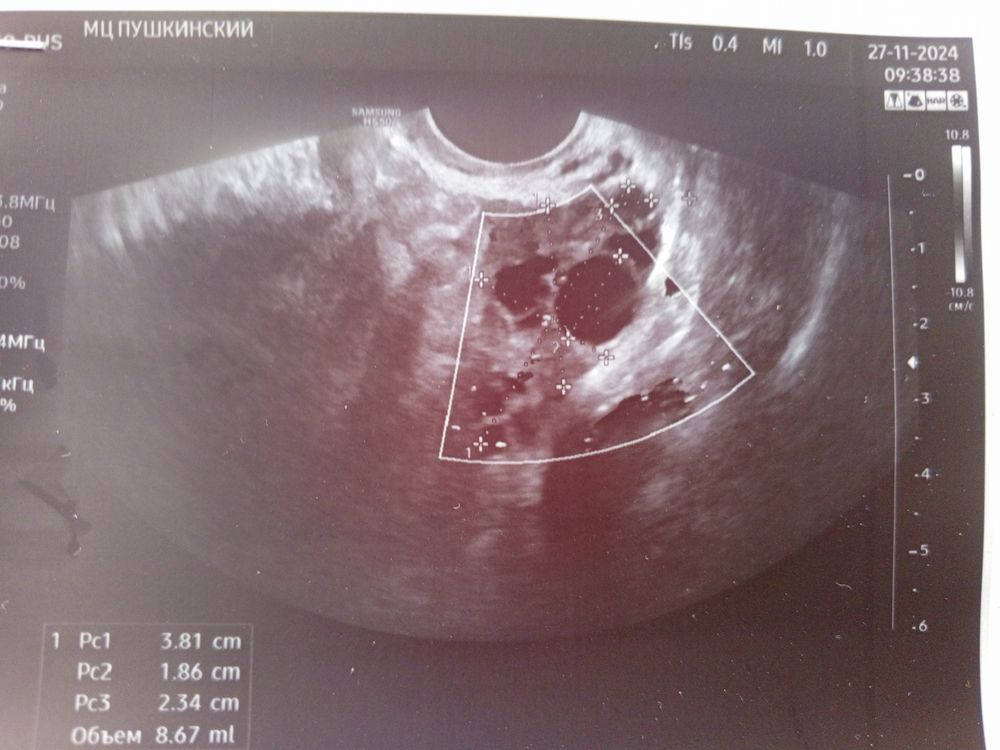

Фолликуламитрию на 13 дц

Первое узи Киста в сосудистом сплетении